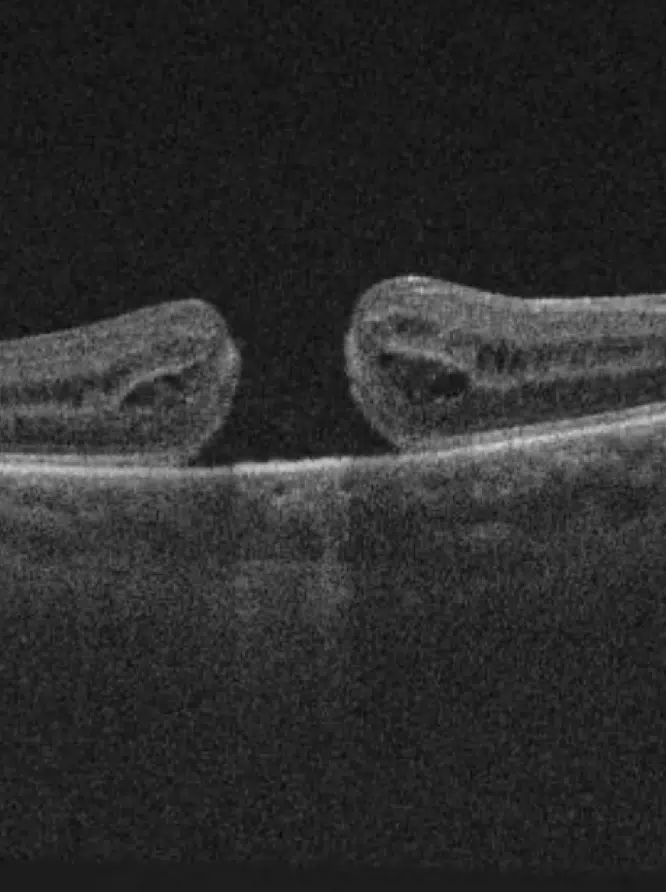

• Une membrane épirétinienne se forme sur la rétine et altère la vision. Pour la retirer, une vitrectomie est pratiquée suivie du pelage de la membrane.

• Un trou maculaire, affectant la macula, peut être traité grâce à une vitrectomie associée à une injection de gaz intraoculaire, favorisant la fermeture du trou et la récupération visuelle.